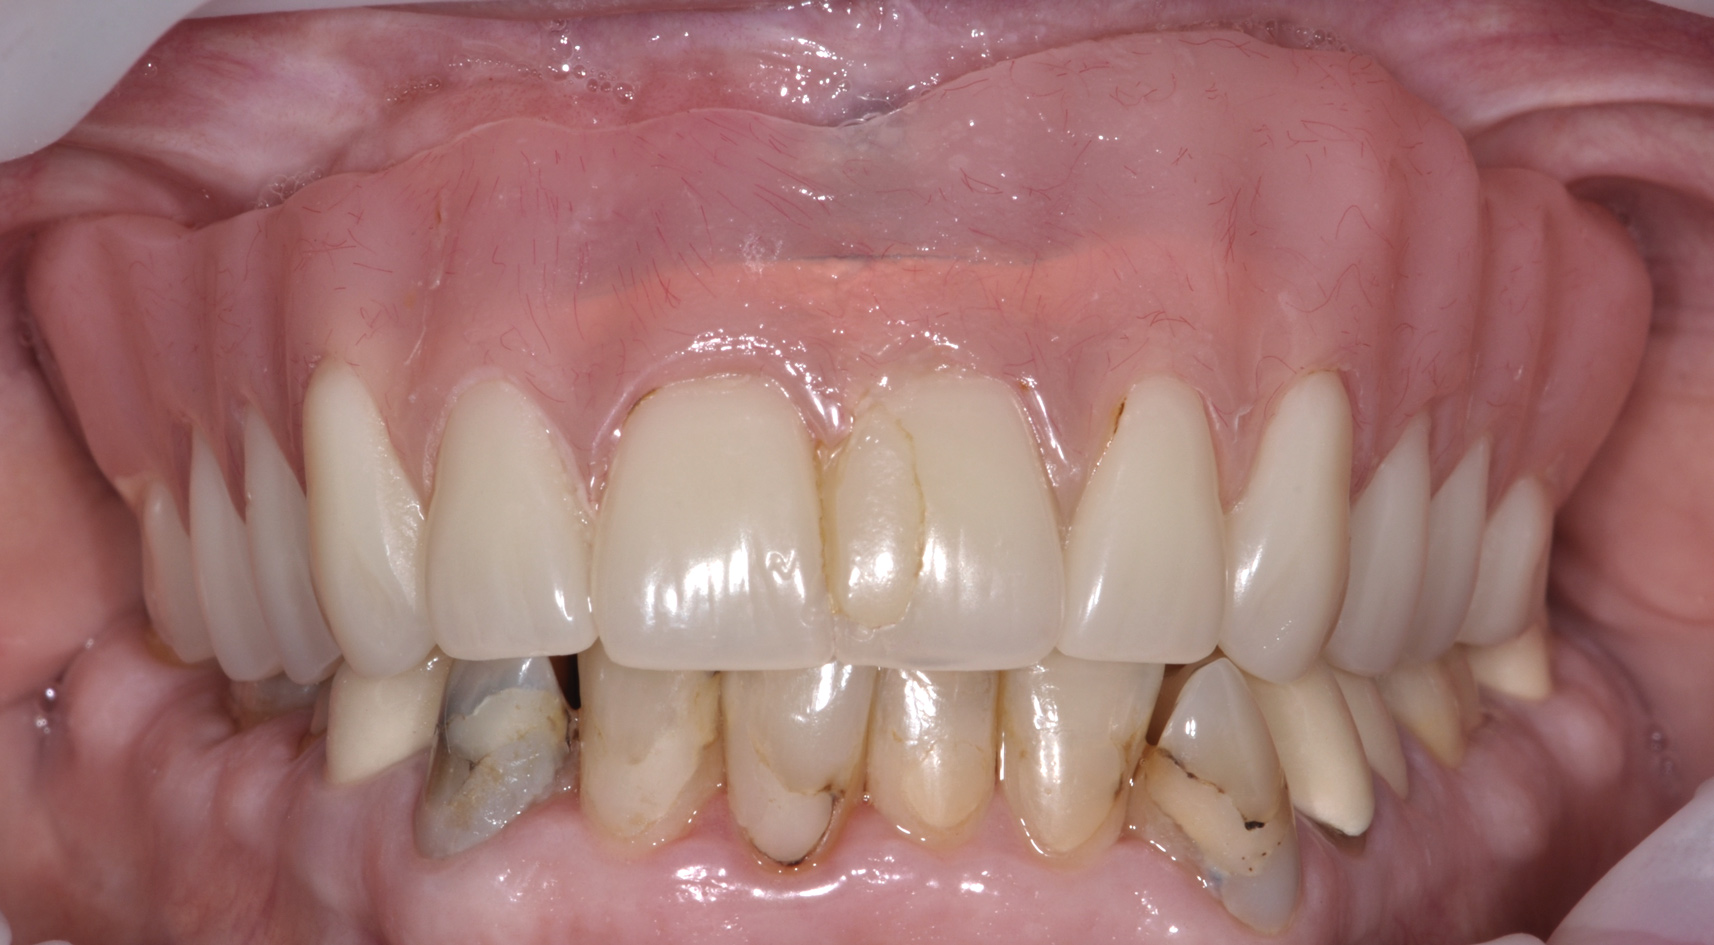

The main objective of peri-implant mucositis treatment is the resolution of inflammation.18 Oral healthcare providers should employ a two-pronged approach in the treatment of peri-implant mucositis. First, they should consider the patient's ability to perform adequate oral hygiene around the implant prosthesisthis includes assessing the patient's accessibility to the area in the mouthand prescribe appropriate aids in biofilm removal (Figure 1 and Figure 2). Second, the clinician should institute mechanical therapy and an appropriate peri-implant maintenance regimen consisting of further evaluation and treatment, if needed.

The clinician should review and reinforce with the patient the patient-administered oral hygiene efforts. Use of an intraoral stain to demonstrate inadequate plaque control has been shown to be effective in patient motivation.19 Nonsurgical peri-implant treatment should consist of mechanical removal of the bacterial biofilms and elimination or control of all local plaque retentive factors. Curettes, sonic and ultrasonic instruments, as well as air polishing with glycine powder are all effective methods of biofilm removal.20 The use of local antibacterials and local or systemic antibiotics appear to have minimal benefit.21 Once the treatment of peri-implant mucositis has been rendered, it is very important that the oral healthcare provider evaluate the response to therapy (Figure 3 and Figure 4). If initial therapy fails to resolve the peri-implant inflammation, it may be beneficial to assess the marginal fit and design of the implant prosthesis with regard to patient access, as well as the possible presence of cement remnants.

Fig 5. In this patient, deep probing depths, suppuration, and bleeding on probing were identified.

Figure 5